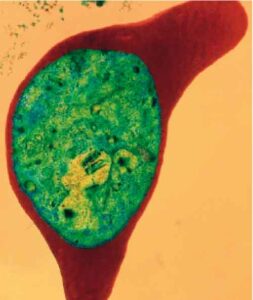

I parassiti della malaria (plasmodi) stanno sviluppando una crescente resistenza all'arthemeter, uno dei derivati dell'artemisina, il farmaco piu' efficace contro...